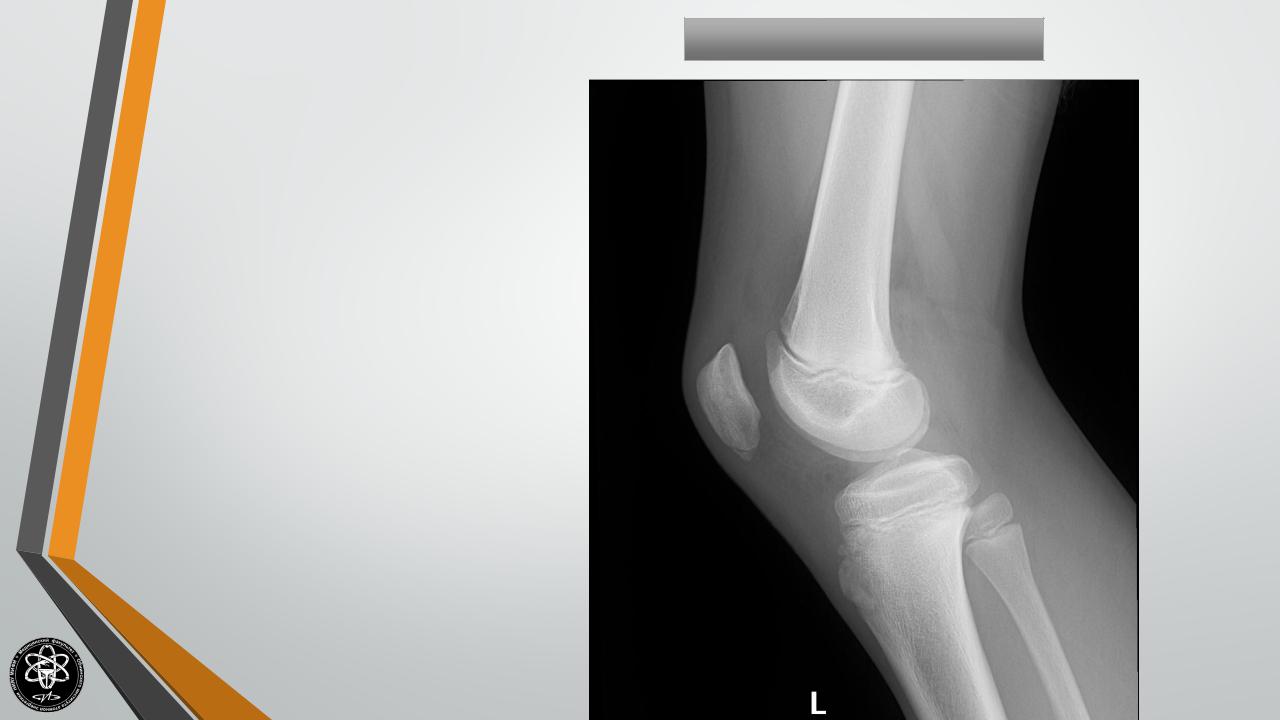

Болезнь Ларсена-Нильсона